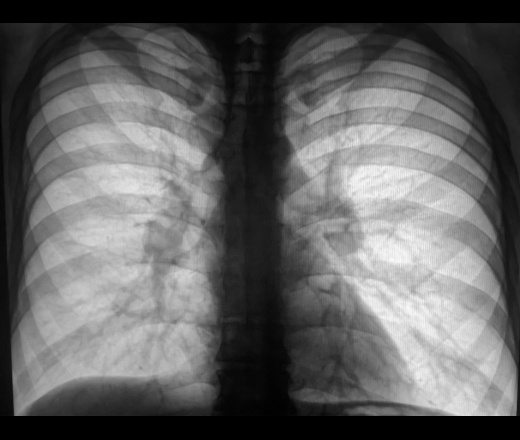

| Рис. 1. Рентгенограмма грудной клетки больного саркоидозом внутригрудных лимфатических узлов. |

Важнейшая роль в выявлении и установлении предварительного диагноза принадлежит рентгенографии; томо- и зонографию легких через плоскость корней с поперечным размазыванием теней, компьютерную томографию используют как уточняющие методы. Основу рентгенологического симптомокомплекса при саркоидозе органов дыхания составляют внутригрудная аденопатия, диссеминация и интерстициальные изменения, обусловленные явлениями альвеолита и пневмосклероза. Для саркоидоза характерно двустороннее увеличение ВГЛУ преимущественно бронхопульмональных групп, хотя в 5 – 8% случаев наблюдают одностороннее поражение, что может вызывать диагностические трудности. Симптом внутригрудной аденопатии наблюдают изолированно при саркоидозе ВГЛУ (рис.1) или в сочетании с изменениями легочной ткани при саркоидозе ВГЛУ и легких (рис.2). Легочная диссеминация характеризуется рассеянными очаговоподобными тенями диаметром от 2 до 7 мм, тяготеющими к плевральным оболочкам и сосудам и более тесно располагающимися в аксилярных зонах. Интерстициальные изменения проявляются мелкосетчатой деформацией легочного рисунка, обусловленной инфильтрацией внутридольковых интерстициальных структур. Часто наблюдают симптом «матового стекла» – диффузное снижение прозрачности легочной ткани – проявление альвеолита.